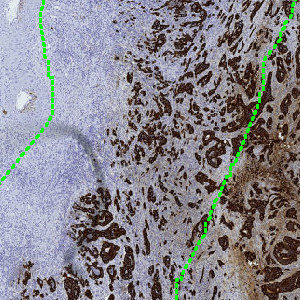

Figure 2

Zoom on the invasive front from FIGURE 1.